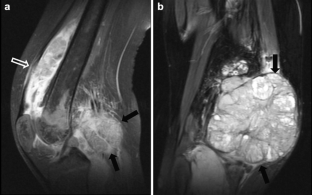

Fig. 3